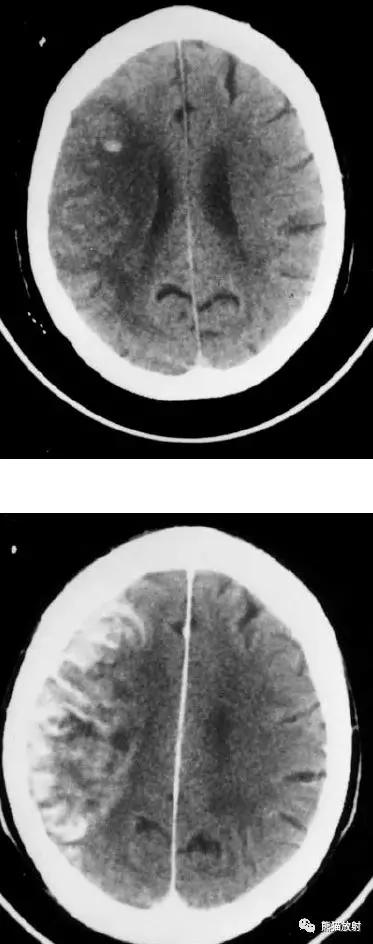

右侧大脑中动脉区域梗死的典型演变:

a)急性期

b)早期亚急性期(2天,从临床起病开始)

c)亚急性晚期(2周后)

d)慢性期(一年后)